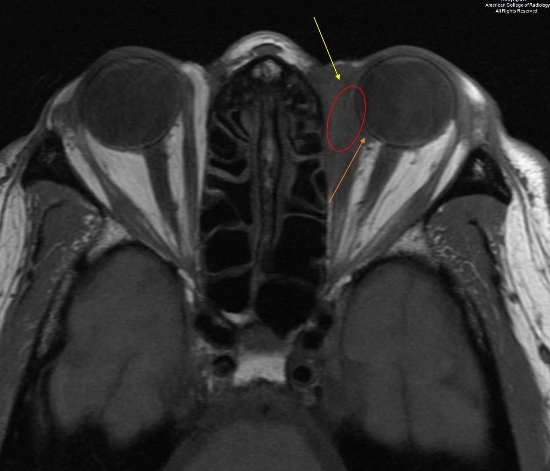

图 2 为平扫横断 T1 ,示病变主要位于眶内肌锥外间隙内(黄色箭头),并累计内直肌及肌腱、眼球筋膜(红色椭圆),蔓延内肌锥间隙内和眶后间隙内(橘黄色箭头)

3.jpg

图 3 为平扫冠状压脂 T1 示,左侧眼眶内上方异常信号(椭圆),与周围脂肪不同,病灶压脂后信号并没有降低

4.jpg

图 4 为增强 T1 压脂冠状位,示上直肌、内直肌、下直肌和上斜肌增粗且强化(红色箭头),外直肌受累不明显(蓝色箭头),并有肌锥外脂肪和眶骨膜浸润性表现(桔色箭头)